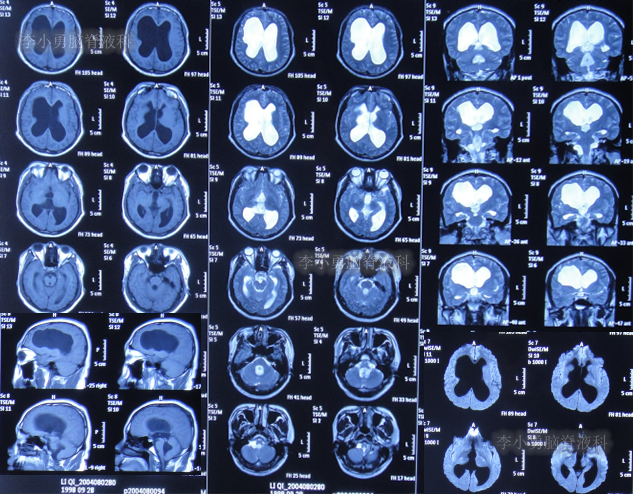

发现脑积水15年后即2020年1月份,开始出现头胀头闷能自行缓解,并没有特殊处理,3月后即2020年4月8日,因症状变重且变频繁,至甘肃省天水市某医院检查头颅核磁(图-3)认为脑积水较前(2016年7月20日头颅CT)加重。

图-3:2020年4月8日头颅核磁

1个月后即2020年5月6日,为治疗脑积水,至陕西省西安市某三甲医院就诊,查头颅核磁示脑积水(图-4)。

图-4:2020年5月6日头颅核磁